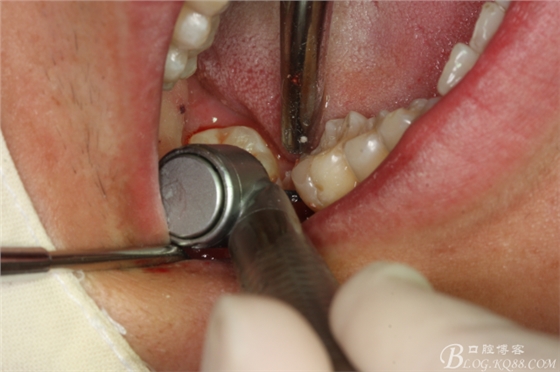

圖13.高速拔牙手機(jī)離斷舌側(cè)牙冠

圖14.挺出47舌側(cè)部分牙冠

圖15.梃子放頰側(cè),以頰側(cè)骨板做支點(diǎn)。挺松47牙根。

圖16.挺出47牙根